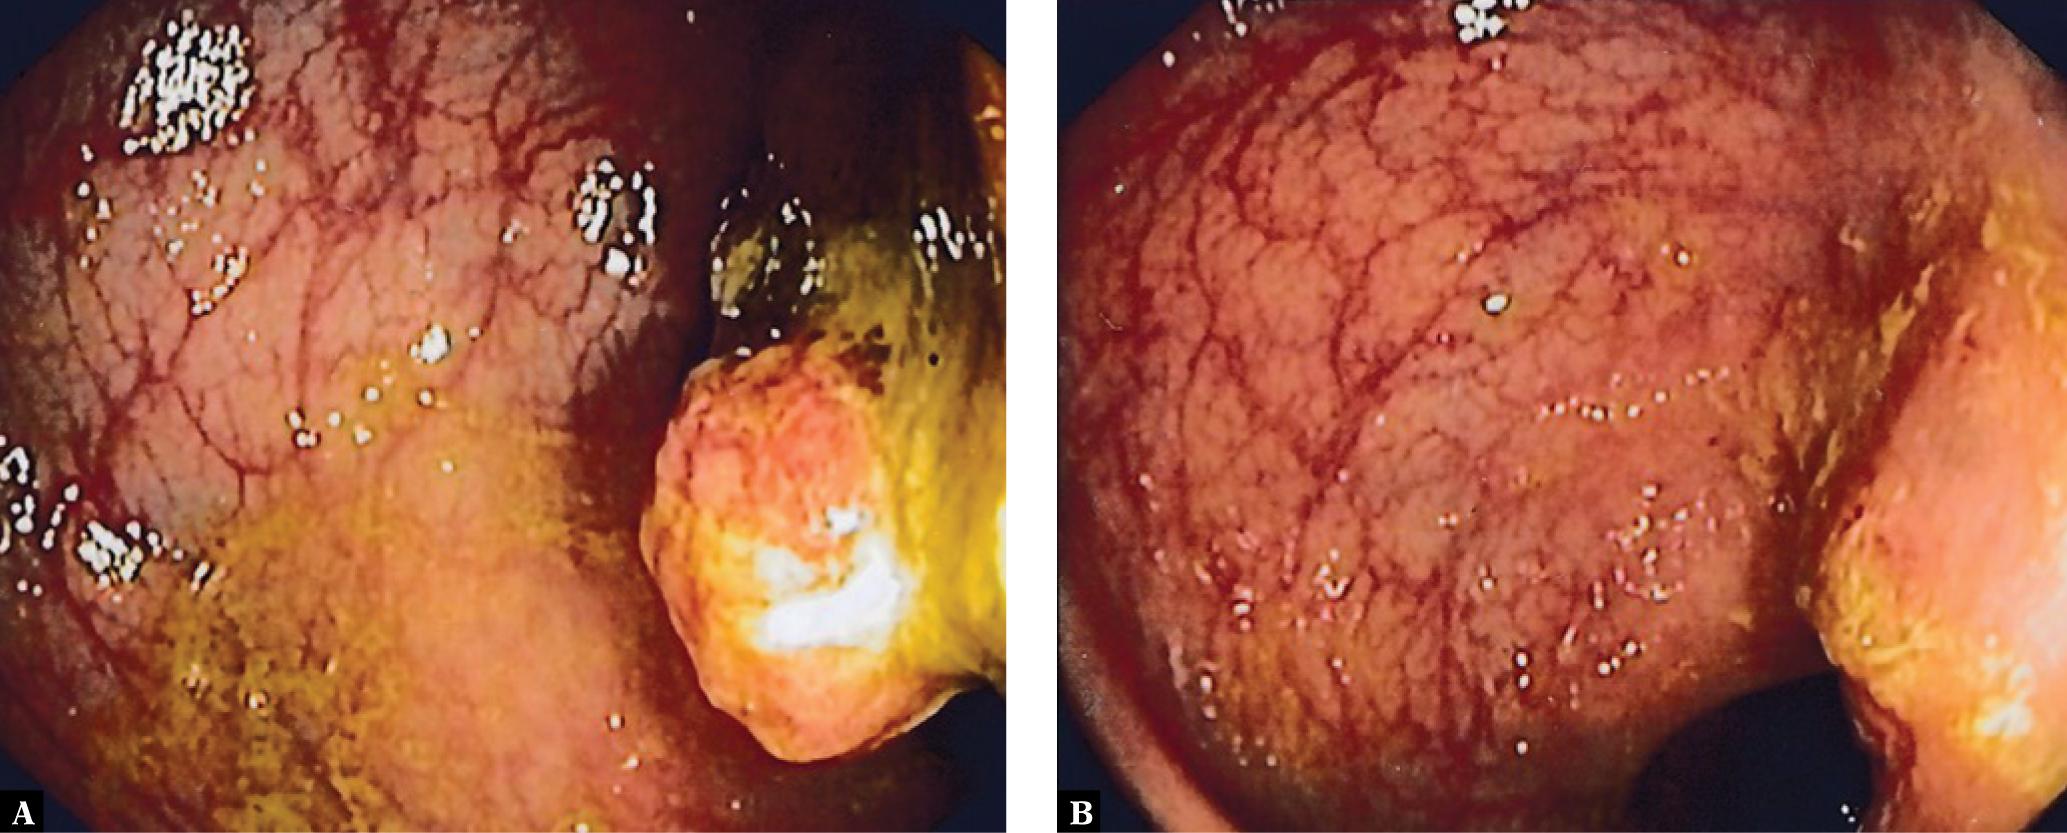

The following figures show transmural endometriosis infiltrating the sigmoid colon and present endoscopy, ultrasound, CEUS and endoscopic ultrasound findings. A 24-year old woman complained of recurrent lower abdominal pain for 6 months. She was referred for colonoscopy. There was no palpable mass on digital rectal examination. Blood chemistry, full blood count, coagulation profile, alfa-fetoprotein and carcinoembryonic antigen were within normal limits. Colonoscopy revealed a semi-circular polypoid lesion in the sigmoid colon suggesting malignancy (Fig. 1). The biopsy taken at colonoscopy was diagnostic for endometriosis and surgical treatment was planned. Other imaging modalities were arranged to stage the local disease and to exclude further manifestations. Transabdominal B-mode ultrasound (BMUS) confirmed a 40 mm sized heterogeneous hypoechoic transmural lesion infiltrating the sigmoid colon (Fig. 2). Contrast enhanced ultrasound showed a rapidly and heterogeneously enhancing lesion during the arterial and venous phases (Fig. 3). Contrast enhanced colour Doppler ultrasound confirmed the finding. Endorectal endoscopic ultrasound of the sigmoid colon revealed transmural extension of the mass and confirmed the transcutaneous finding (Fig. 4). The lesion was well vascularized (Fig. 2 and Fig. 4). Magnetic resonance imaging did not add any additional information. Subsequently, the patient underwent laparoscopic sigmoid resection. Pathological examination revealed extragenital endometriosis. Microscopic examination disclosed endometrial stroma and gland islands located between muscular fibres, subserosa and serosa. The postoperative period was uneventful.

Colonoscopy showed a semicircular polypoid lesion in the sigmoid colon suggesting neoplasia (A). The lesion was partially resected by endoscopic mucosal resection for tissue sampling (B)